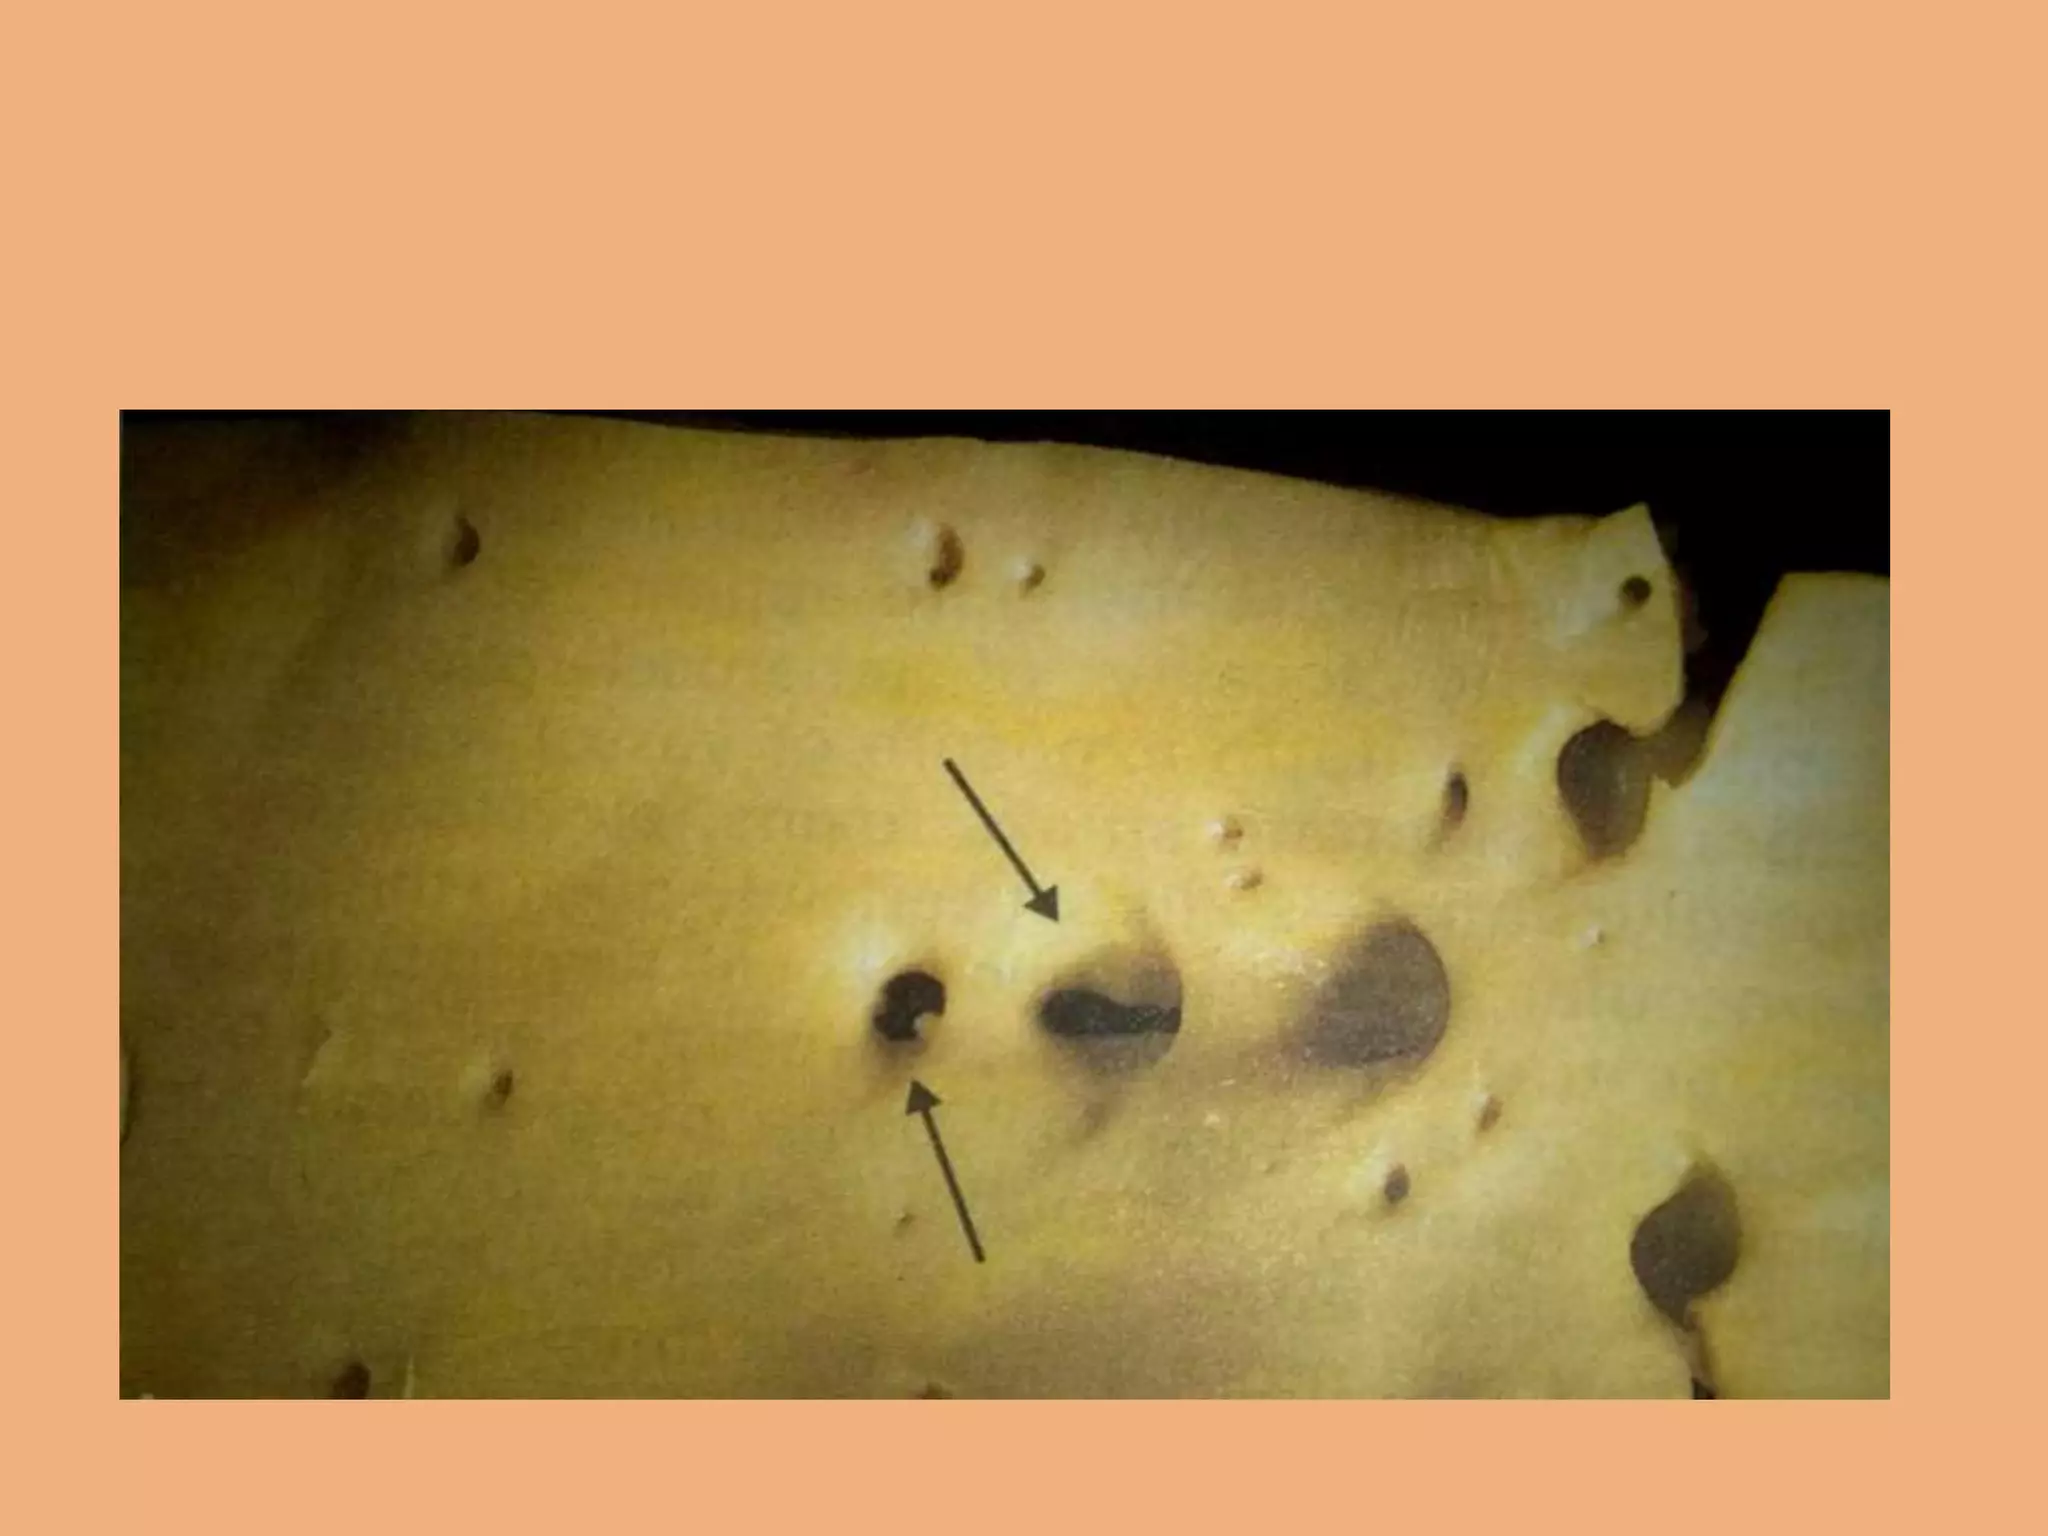

Remote myocardial infarction (weeks to years)

Myocardial Rupture

Myocardial aneurysm with

thrombosis inside.

Rupture (at the arrow) into the pericardial sac can produce a life-

threatening cardiac tamponade, as seen here. The septum may also

rupture.

Rupture (at thearrow) into the pericardial sac can produce a life- threatening cardiac tamponade, as seen here. The septum may also rupture.